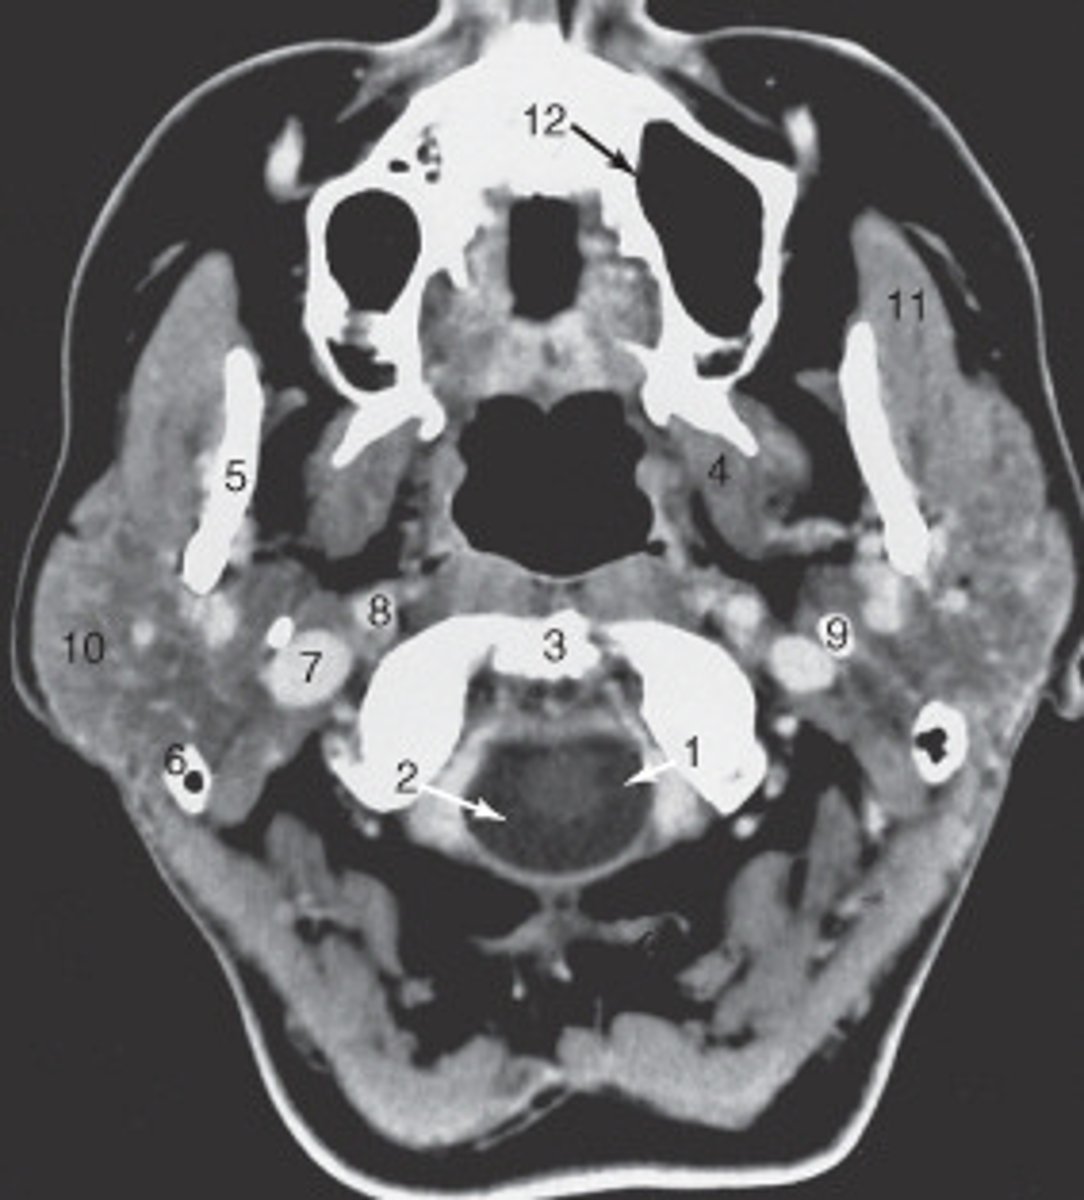

the nasal septum is labeled:

<p>the nasal septum is labeled:</p>

the mastoid air cells are labeled:

<p>the mastoid air cells are labeled:</p>

the structure labeled 6 is the:

<p>the structure labeled 6 is the:</p>

the structure labeled 5 is the:

<p>the structure labeled 5 is the:</p>

the zygoma is labeled:

<p>the zygoma is labeled:</p>

the lateral orbital wall is labeled:

<p>the lateral orbital wall is labeled:</p>

the structure labeled 3 is the:

<p>the structure labeled 3 is the:</p>

the structure labeled 7 is the:

<p>the structure labeled 7 is the:</p>

The sphenoid sinus is labeled:

<p>The sphenoid sinus is labeled:</p>

The internal jugular vein is labeled:

<p>The internal jugular vein is labeled:</p>

the parotid gland is labeled:

<p>the parotid gland is labeled:</p>

the structure labeled as 8 is the:

<p>the structure labeled as 8 is the:</p>